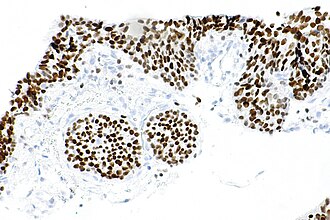

GATA3 staining in benign urothelium. | |

| Normal staining pattern | nuclear |